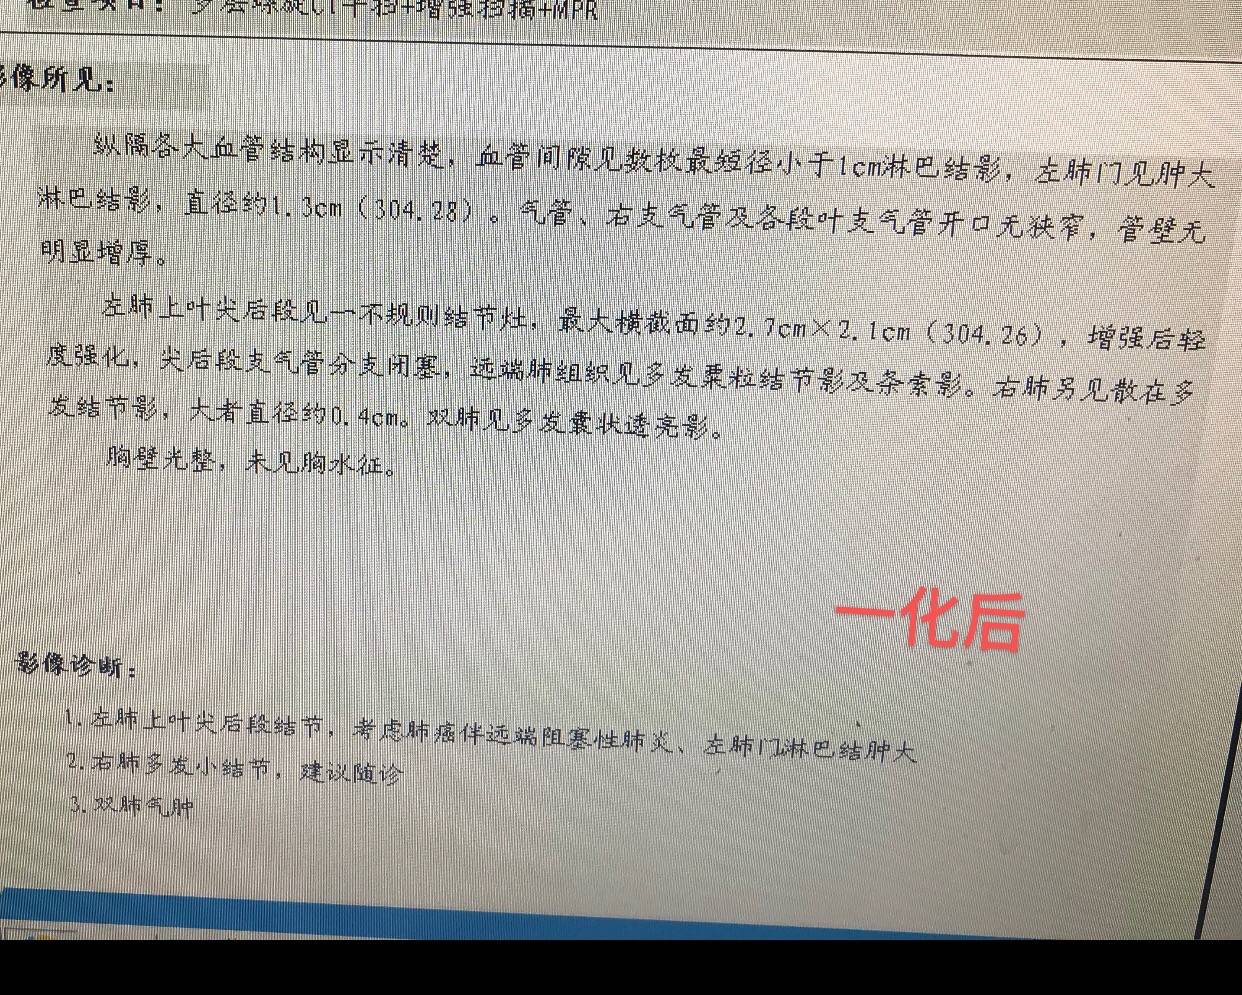

因为出现心肌酶略增高,三化效果不错,病灶仅剩"少许软组织影"了,故决定抓紧手术。

大家可以注意一下这里,原发灶变成少许软组织影,提示明显变小了,但为什么淋巴结增多,增大呢?

免疫治疗效果很好,淋巴系统激活活跃的话,淋巴结也增大,谓之假进展。

所以陈某人也支持继续手术

术后拟对纵隔淋巴结区域放疗

等待手术的过程中,患者怕淋巴结区域继续进展,就在另一家医院就近又复查了CT

结果出来惊得患者目瞪口呆

报告竟然报术后改变

患者没有做手术呀!

患者很惊讶!莫非拿错报告了?发生了左腿切右腿,男性报告有卵巢这种荒谬的事情

经过陈某某核对,图像确实是患者的

然后陈某某告诉说,患者"痛失"手术机会了!

后续可以先免疫维持,如果病情出现变化,后续再出现病灶的时候再考虑手术。